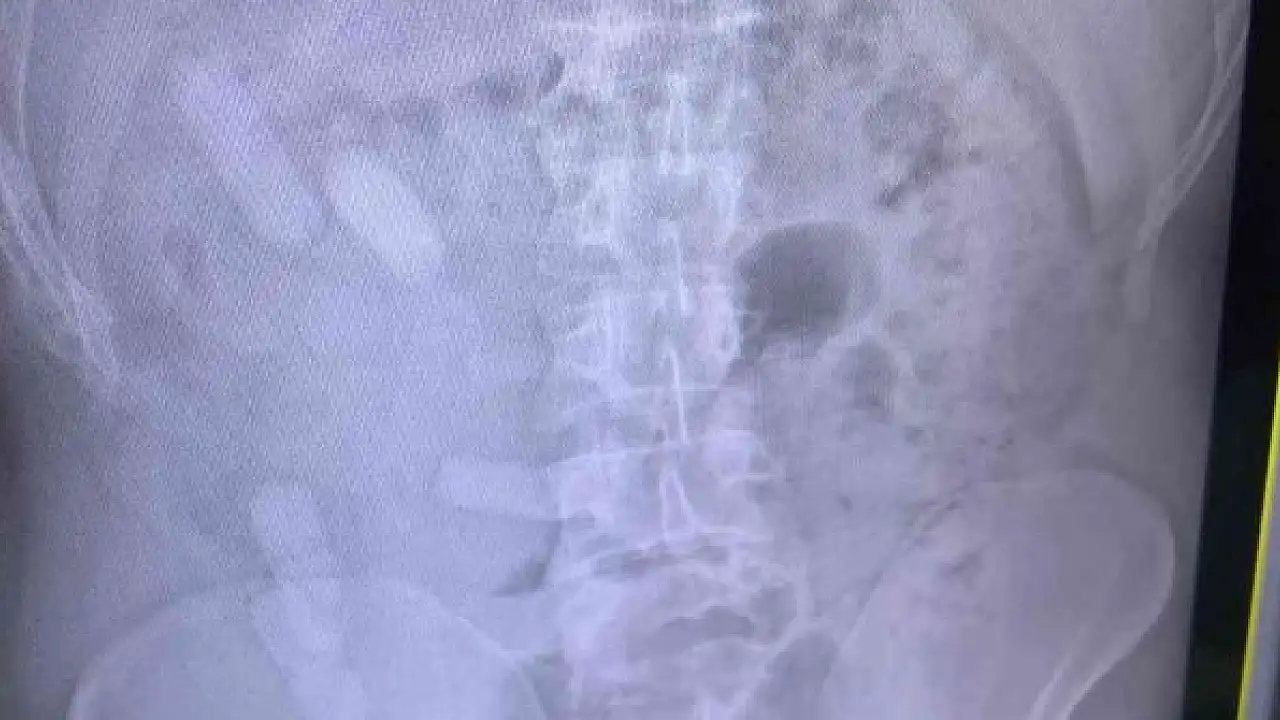

Edinilen bilgiye göre Sivas İl Jandarma Komutanlığı ekipleri, D-100 karayolu Yıldızeli ilçesi geçişinde Lasy isimli narkotik köpeği ile yol denetimi gerçekleştirdi. İranlı yolcuları taşıyan 84 AA 845 plakalı otobüste yapılan aramada A.E. (34) isimli şahsın üzerinde, içerisinde reçine esrar bulunan 140 kapsül ele geçirildi. Şüphe üzerine A.E. isimli İranlı şahsa çekilen röntgen filminde midesinde de 15 kapsül olduğu anlaşıldı. Kapsüller doğal yollarda çıkartıldı. A.E. jandarma ifadesinin ardından çıkartıldığı adli makamlarca tutuklanarak cezaevine konuldu.